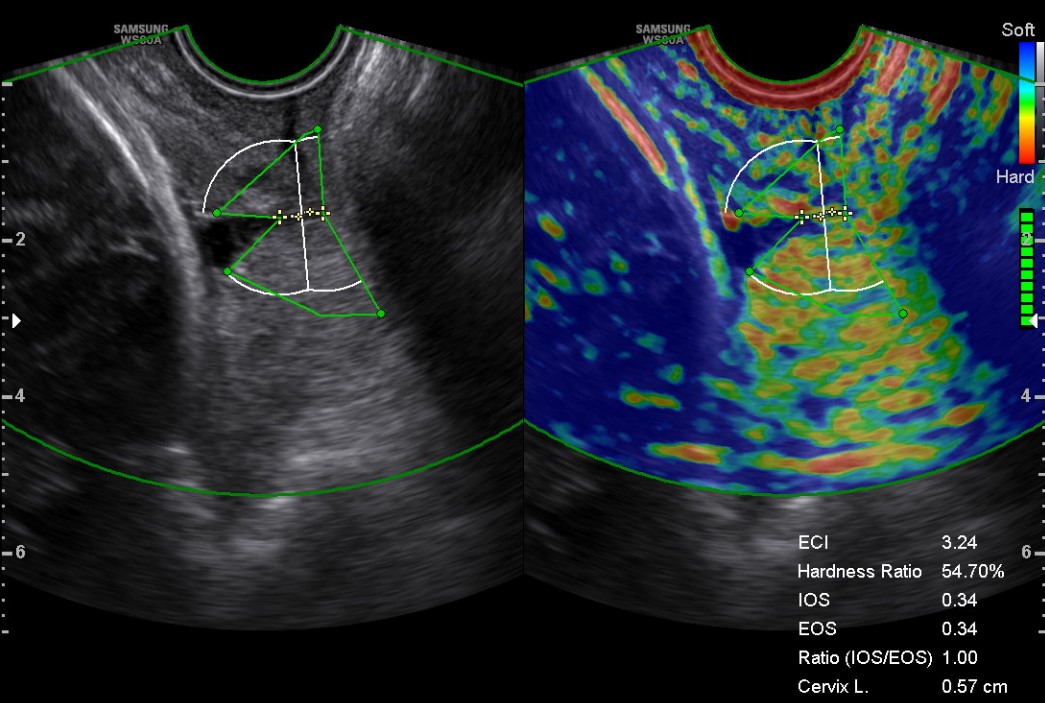

A standardized protocol was employed for measuring cervical length and assessing cervical elastography through E-Cervix. A transvaginal probe (3–10 MHz) connected to the Samsung HERA W10 ultrasound system (S2SKM3HW20000SE, Gangwon-do, Korea) was utilized, with the E-Cervix software (1.03.00a.3009, Seoul, Korea) activated. This was conducted by an experienced sonographer who had received training on the use of the E-Cervix program before labor induction. After emptying the bladder, the subjects remained still and breathed slowly and steadily. Measurements taken included the cervical length, the cervical hardness ratio, the shape of the internal cervical os, the transverse width of the cervix, and the IOS/EOS ratio (internal and external cervical oral strain ratio). As shown in Fig. 1.

Fig. 1.

Transvaginal grayscale sonography and elastography images. The basic characteristics of this pregnant woman: 29 years old, height 1.64 m, 40 weeks gestation, pre-delivery body mass index (BMI) 24.91 kg/m2, weight gain 9 kg during pregnancy. The Bishop score: 5. Cervical elastography ultrasound parameters: cervical length 0.57 cm, cervical hardness ratio 54.7%, cervical internal opening shape Y, cervical transverse width 0.9 cm, internal/external os (IOS/EOS) ratio 1. ECI, elasticity contrast index; Cervix L, cervical length.